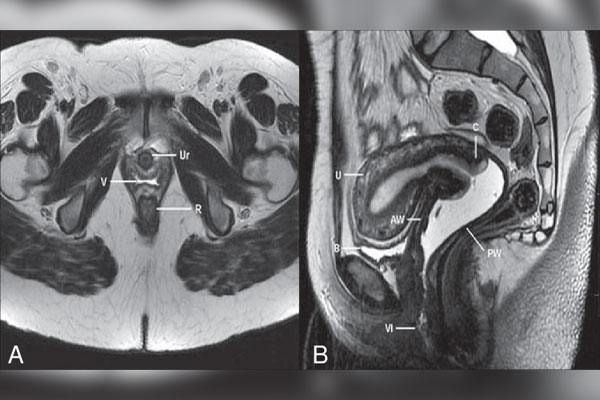

نوبت دهی ام آر آی کف لگن

تصویربرداری

1404/12/02

ام آر آی کف لگن از امواج مغناطیسی و امواج رادیویی برای تصاویر با کیفیت بالا و دقیق از ساختارهای کف لگن استفاده میشود....